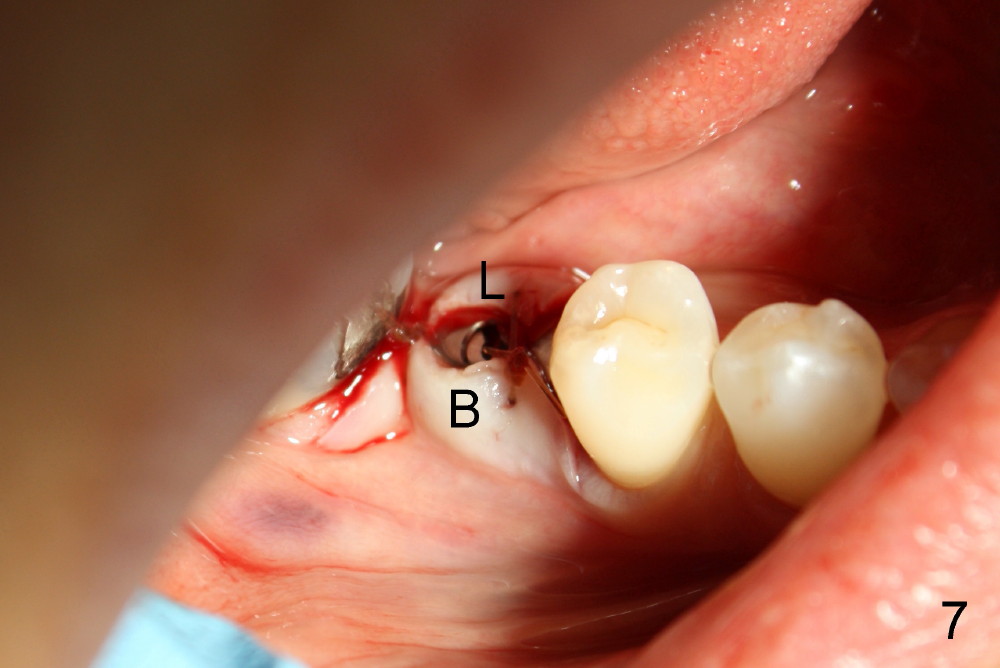

切口翻瓣(颊(B)舌(L)侧)后,证实骨头宽度(图三)。为了掌握好深度,术前术中多拍摄X光片几次,并且进行测量,反复问自己看清楚神经没有(与否):神经管上缘在那里?如果没有把握,宁可用短一些植牙,给自己多一些余地。其实植牙长度不重要,而直径更重要。

这一例由于病人条件好(骨头宽),术前准备工作充足,术中小心翼翼,最终结果还比较理想(图六):植牙(I:6x14毫米)离神经(N)以及颏神经襻(*)两到三毫米。最后缝合伤口(图七)。由于这位病人口腔卫生维持的好,第二前臼齿刷的干干净净,术后没有用抗生素。现在术后第四天还没有感染或者神经受损迹象。